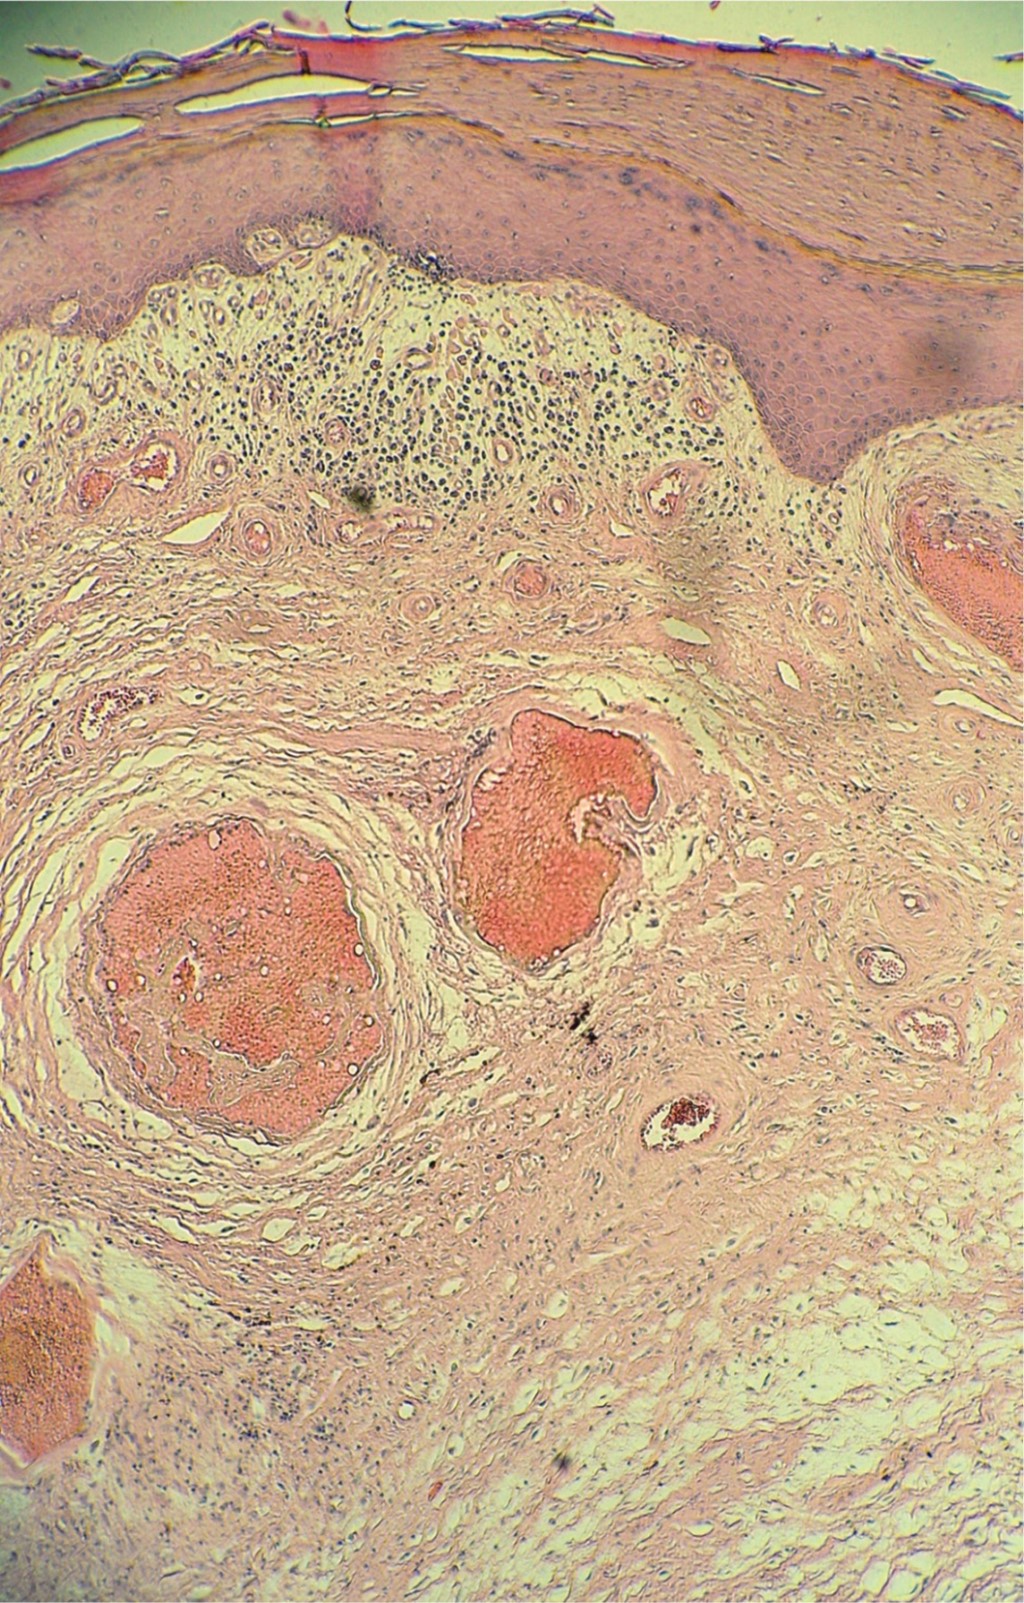

Figure 1